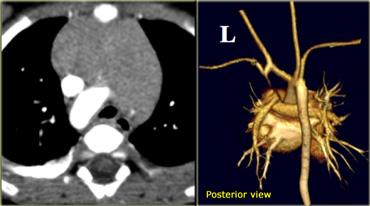

On the left a chest film of a young adult with a cough.

On the left axial images and posterior view of volume rendered reconstruction.

Describe the findings and then continue.

The findings are:

- four vessel sign

- double arch

- right arch higher and larger

- esophagus and trachea are completely encircled

The narrowing of the trachea is seen on the axial images, but better appreciated on the MPR and Volume Rendered image.